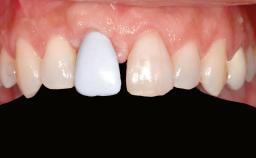

Ridge Preservation and Implant Placement for a Fixed Dental Prosthesis After a Car Accident

It is well known to clinicians that any removal of teeth will, over time, cause the dimensions of the alveolar ridge to be reduced by resorption of the bundle bone and by changes related to external modeling. This development is particularly evident in the crestal region with its thin buccal bone that consists of bundle bone almost entirely. The facial bone will rapidly resorb as blood supply from the periodontal ligament gets disrupted (Araújo and Lindhe 2005). There is no reason why traumatic tooth loss should not have the same consequences. It takes more than achieving implant osseointegration for a treatment outcome to be considered successful. No deficiency of bone or soft tissue is acceptable when an ideal esthetic outcome is the goal. Several articles (Sanz and coworkers 2011; Vignoletti and coworkers 2011) have reported on techniques of improving the alveolar ridge for implant treatment, notably focusing on protecting tissues from resorption.

Prosthesis Type FDP

Patient's Esthetic Expectations Low Medium High

Esthetic Risk High